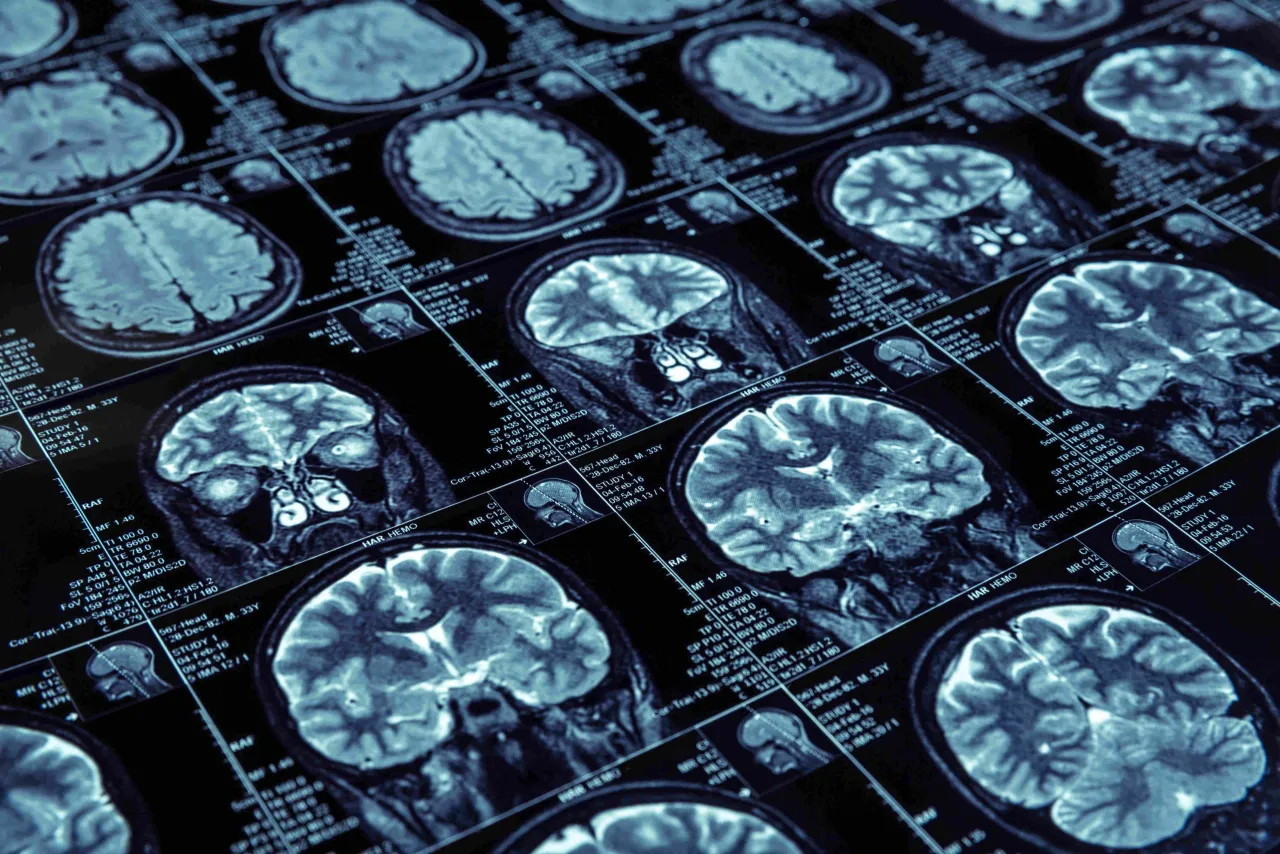

Tomografia komputerowa (TK) głowy to zaawansowane badanie obrazowe, które wykorzystuje promieniowanie rentgenowskie do stworzenia szczegółowych, przekrojowych obrazów struktur wewnątrzczaszkowych. Wyobraźmy sobie, że urządzenie wykonuje setki zdjęć rentgenowskich pod różnymi kątami, a następnie komputer składa je w trójwymiarowy obraz. Dzięki temu możemy zajrzeć w głąb mózgowia, kości czaszki, naczyń krwionośnych oraz tkanek miękkich. Jest to badanie niezwykle szybkie i nieinwazyjne, co czyni je niezastąpionym narzędziem diagnostycznym, szczególnie w sytuacjach wymagających natychmiastowej oceny stanu pacjenta.

Często spotykam się z pytaniem, jaka jest różnica między tomografią komputerową a rezonansem magnetycznym (MRI) i które badanie jest lepsze. Otóż, oba są doskonałymi narzędziami diagnostycznymi, ale mają różne zastosowania i wzajemnie się uzupełniają. Tomografia komputerowa jest szybsza i znacznie lepiej uwidacznia struktury kostne, takie jak kości czaszki, a także świeże krwawienia. Z tego powodu jest badaniem z wyboru w stanach nagłych, na przykład po urazach głowy czy przy podejrzeniu ostrego udaru mózgu, gdzie szybka diagnoza jest kluczowa. Rezonans magnetyczny natomiast oferuje znacznie dokładniejszy obraz tkanek miękkich mózgu i jest czulszy w wykrywaniu subtelnych zmian, takich jak wczesne ogniska udaru niedokrwiennego, stwardnienie rozsiane czy niektóre typy guzów. Podsumowując, TK jest niezastąpiona w nagłych przypadkach i ocenie kości, natomiast MRI w bardziej szczegółowej diagnostyce zmian w samym mózgu.